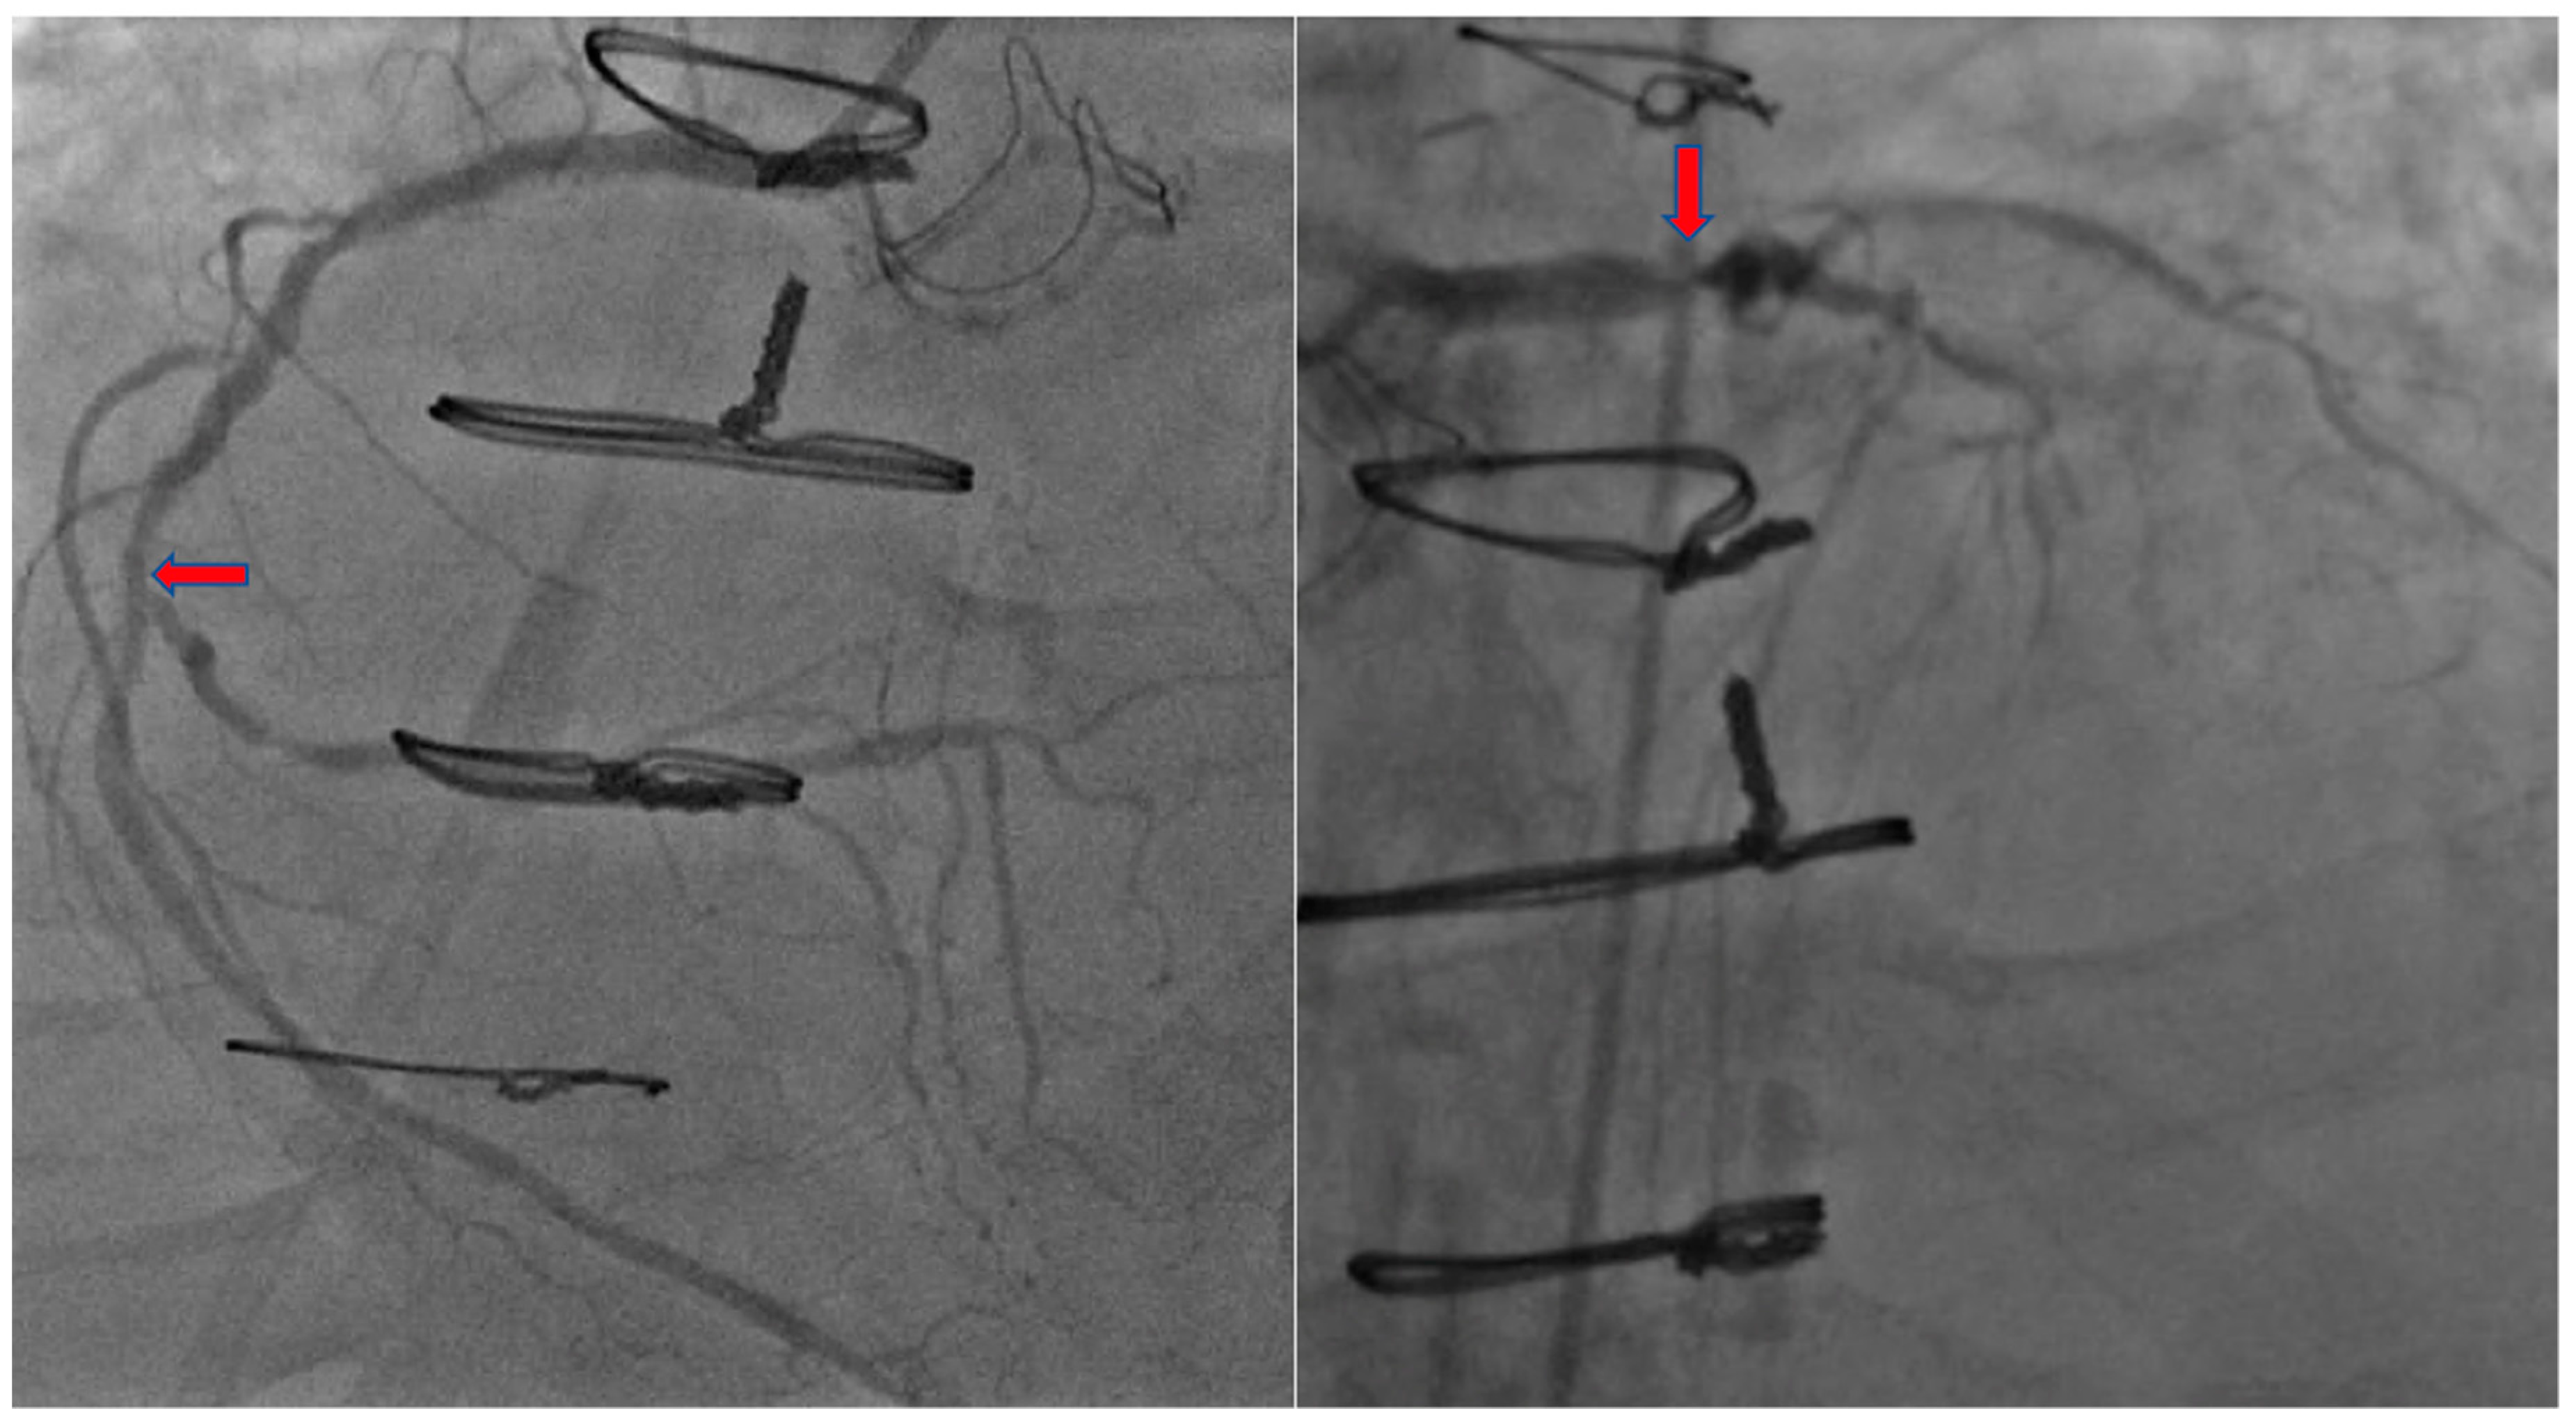

2. Case Presentation